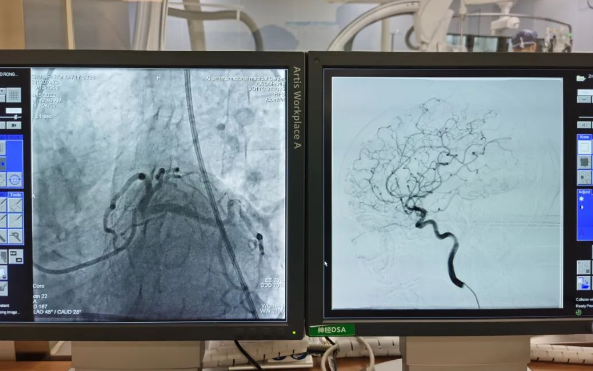

術(shù)前準(zhǔn)備就緒后,心內(nèi)二病區(qū)曾廣偉主任、高釗副主任醫(yī)師、神外科陸丹副主任醫(yī)師共同為患者行腦血管造影術(shù) 冠狀造影術(shù)。術(shù)后,朱奶奶恢復(fù)良好。

陸丹副主任醫(yī)師介紹,由于腦血管疾病和心血管疾病有著共同的病理變化基礎(chǔ)——?jiǎng)用}粥樣硬化,臨床中,兩類疾病交叉存在的情況十分多見(jiàn)。“心腦同治”的模式不僅能讓患者獲得較好治療,還能夠降低患者就醫(yī)的時(shí)間成本和經(jīng)濟(jì)成本。